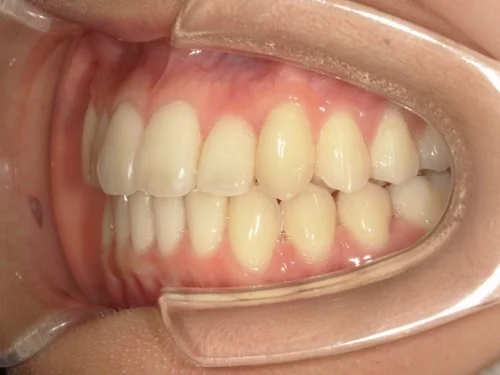

<症例7>歯がガタガタで噛み合わせが悪くお悩み

抜歯無し・マウスピースのみで矯正した症例です。

もともと歯列弓が非常に狭く、V字に近い形をしていたので噛み合わせも非常に不安定でした。

また、下顎前歯部がかなり上の方に生えていたため、下の前歯が上の前歯を突き上げてしまい出っ歯の状態になっていました。

現在では見た目はもちろん、臼歯の噛み合わせも改善しております。

奥歯の患者様も大喜びでした。

患者様と症状

主訴:歯のガタガタ、噛み合わせが悪い

性別・年齢:20代女性

問題点:叢生(重度)、V字歯列弓、ディープバイト

診断:前歯部の叢生を伴うアングルⅠ級、骨格性Ⅰ級の不正咬合

主なリスク:臼歯の移動に伴い一時的に咬合しにくくなる、歯肉退縮

症状:叢生(そうせい) 過蓋咬合(かがいこうごう)

治療内容

治療期間:1年10ヶ月

治療費用:990,000円(税込)

プラン:Full2プラン

抜歯:無し

再診治療費:無し

追加治療費:無し

保定装置費:無し

治療前後の写真